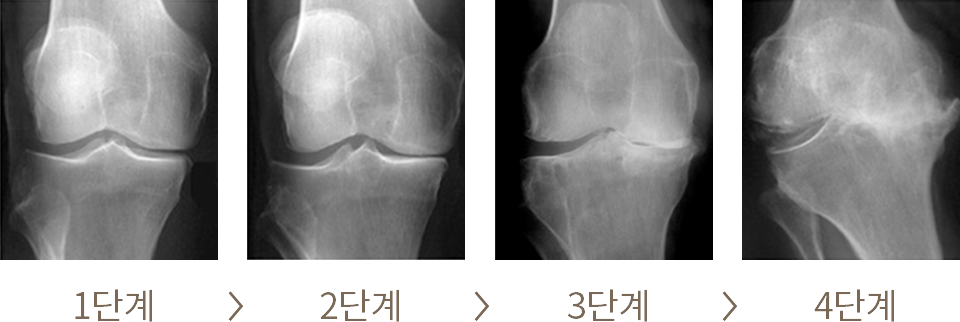

Osteoarthritis (OA)

무릎의 퇴행성관절염의 진행 단계

퇴행성관절염으로 인한 관절 변형